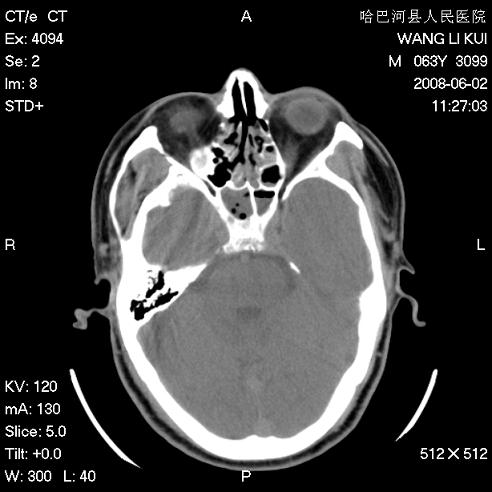

标题: CT13803:反复性鼻塞、流涕一年余 [打印本页]

标题: CT13803:反复性鼻塞、流涕一年余

副鼻窦炎,右上额窦积脓。左眼肌锥内见致密影,视神經受压

全组副鼻窦炎 肌锥内高密度灶。建议进一步检察检查

1、全组副鼻窦炎。

2、左眼眶肌锥内病变,小血管瘤?建议增强。

1)全副鼻窦炎(左侧上颌窦黏膜下囊肿或息肉)。2)左眼眶肌锥内不规则小结节状软组织密度影;考虑为小血管瘤可能。建议行ct增强扫描检查。

全组副鼻窦炎,左侧肌锥内不规则形软组织肿块影,与眼外肌密度相当,左侧视神经受压,肿块与视神经及眼外肌分界清晰,眼外肌无增粗,眶壁无破坏,球后脂肪间隙不模糊,考虑良性改变,小血管瘤或神经源性肿瘤可能,建议增强扫描。

谢谢,增强扫描做了,眶内病灶与海绵窦同步明显强化,血管瘤